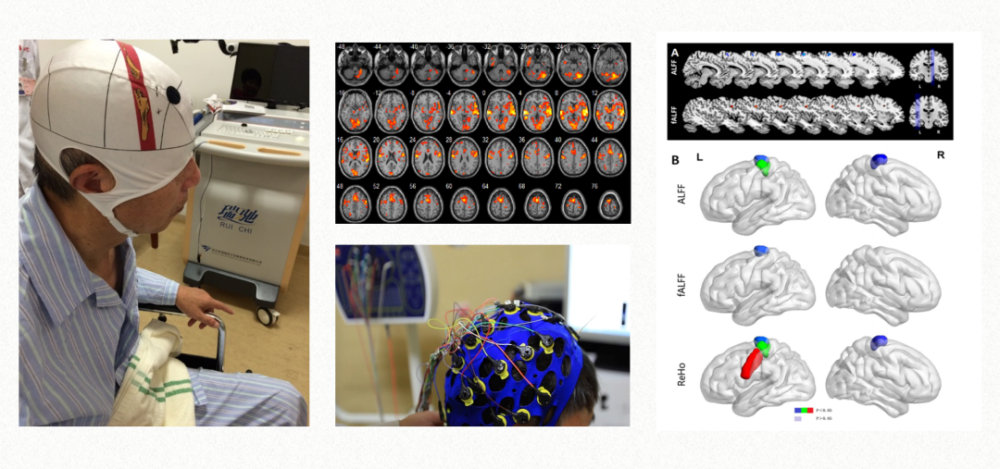

文章插图

神经调控技术在临床康复已经广泛应用 。

康复科每年会收治较多包括外伤、自发性脑出血、心脏骤停等各种原因引起的意识障碍患者 。 患者入院后 , 我们会给予包括常规床边神经行为学检查、脑电图、脑干诱发电位、脑部功能性核磁共振等在内的全面完善评估 , 做到精准评估 。 然后基于这些评估结果制定个性化康复治疗方案 。 通过多感觉综合刺激、脑部神经调控技术、康复机器人、药物等进行康复治疗 。

科室积极开展康复评估与康复治疗新技术 , 包括超声/肌电图/电刺激定位引导下的肉毒毒素注射、肌骨超声、重复经颅磁刺激、经颅直流电刺激、上下肢康复机器人、步态分析、平衡测试及训练、动态肌电图、近红外脑功能成像技术、脑电图及诱发电位、虚拟现实技术、脑机接口技术等 。 得益于这些新技术的应用 , 使精准化康复成为可能 。